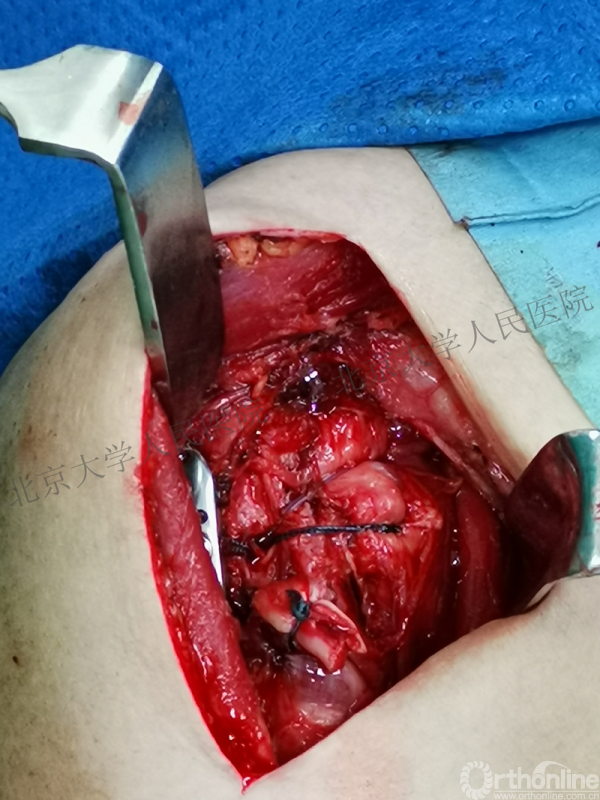

全麻下行切开复位内固定术,备植骨+关节镜检

(关节镜准备是必要时修复后盂唇)

胸大肌三角肌间隙入路

操作步骤